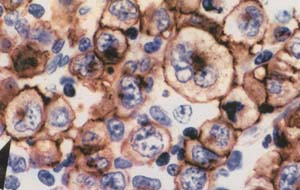

- ESTUDIO CON MARCACIONES